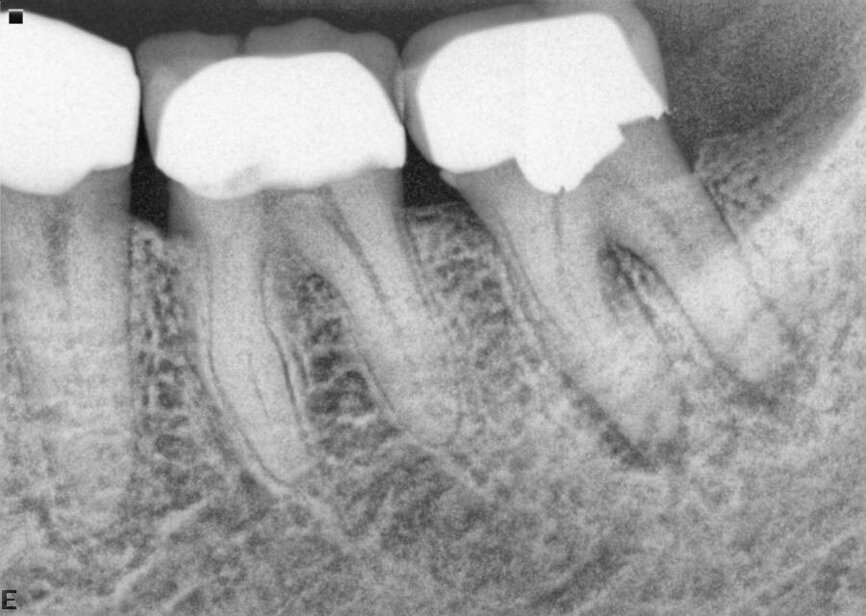

Fig. 17a: Case assisted with CBCT to determine anatomy pre-operatively. Note the multiple cross sections moving apically and the correlation to the 2-D view. Note also the conservative taper in relation to the root width. (Courtesy of Dr. Brett Gilbert)

Fig. 17b: Case assisted with CBCT to determine anatomy pre-operatively. Note the multiple cross sections moving apically and the correlation to the 2-D view. Note also the conservative taper in relation to the root width. (Courtesy of Dr. Brett Gilbert)

Fig. 17c: Case assisted with CBCT to determine anatomy pre-operatively. Note the multiple cross sections moving apically and the correlation to the 2-D view. Note also the conservative taper in relation to the root width. (Courtesy of Dr. Brett Gilbert)

Fig. 17d: Case assisted with CBCT to determine anatomy pre-operatively. Note the multiple cross sections moving apically and the correlation to the 2-D view. Note also the conservative taper in relation to the root width. (Courtesy of Dr. Brett Gilbert)

Fig. 17e: Case assisted with CBCT to determine anatomy pre-operatively. Note the multiple cross sections moving apically and the correlation to the 2-D view. Note also the conservative taper in relation to the root width. (Courtesy of Dr. Brett Gilbert)

Fig. 17f: Case assisted with CBCT to determine anatomy pre-operatively. Note the multiple cross sections moving apically and the correlation to the 2-D view. Note also the conservative taper in relation to the root width. (Courtesy of Dr. Brett Gilbert)

Managing complex anatomy is much simpler if the clinician has a pre-operative road map. The CBCT provides the roadmap and the surgical microscope the lens (literally) through which to visualize the result. Aside from a relaxed patient who is profoundly numb, being able to visualize anatomy by taking a pre-operative (and possibly intra-operative) CBCT and using a surgical microscope during treatment have no substitutes. They are the current “Gold Standard” in that 3-D imaging shows the clinician the true reality of a clinical situation as opposed to the suggestion gained from a 2-D radiograph. Proper interpretation of imaging prior to and/or during endodontic treatment goes a long way in taking the “guesswork” out of identifying canal location and other anatomical complexities as the procedure unfolds. In a 2014 study by El Fayad and Johnson, it was determined that when having a pre-operative CBCT as compared to 2-D radiographs alone, the treatment plan was modified 62 percent of the time. This is a huge game changer to think that the information learned from 3-D imaging changed the plan of treatment over six times out of 10 (Fig. 4).[2]